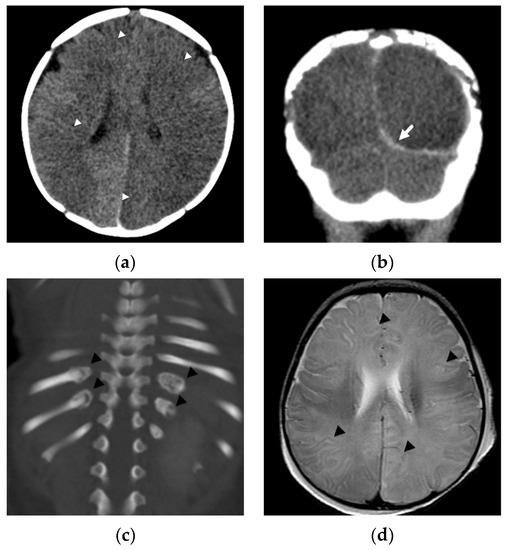

These diffuse, hemispheric patterns of injury/insult are observed in abusive head injury much more commonly than in cases of accidental pediatric head trauma [22,24], suggest permanent brain injury, and portend a poor outcome [22,23,24] (Figure 1). Except in cases of significant accidental trauma, such as pedestrians hit by cars or motor vehicle accidents, this type of injury is not found in children with more routine, household injuries [34], such as a short fall from a couch. In a comparative study looking at DWI in young children with abusive (n = 30) and accidental (n = 22) injuries, Ichord et al. [24] found that patients in their series with abusive injuries much more commonly demonstrated a pattern of restricted diffusion concerning for hypoxic-ischemic injury than those suffering accidental injuries (37% versus 9%). Nine of thirty abused patients demonstrated a predominantly diffuse pattern of parenchymal injury with a coexistent, small-volume subdural hemorrhage or other traumatic lesion compared with only 1/22 of accidental cases. Their patients with these diffuse insults tended to be younger in age, had greater acute and chronic neurologic abnormalities, and a higher likelihood of requiring longer-term inpatient rehabilitation.

Figure 1.

Subdural hemorrhage and subdural collections in an unresponsive 2-month-old male presenting with forehead bruising and respiratory depression. (a) Axial noncontrast head CT image demonstrates thin, high attenuation subdural hemorrhage along the posterior left occipital lobe (black arrow) and bilateral, low attenuation frontal subdural collections (white arrowheads). There is also subtle loss of gray-white matter differentiation bilaterally; (b) axial T2-weighted MR image on day 4 shows regions of decreased gray-white matter differentiation throughout both cerebral hemispheres with T2 hyperintense subdural collections (white arrowheads) and hypointense subdural hemorrhage posteriorly (white arrows); (c) axial b-1000 diffusion-weighted image demonstrates diffuse areas of abnormal, restricted diffusion (white arrowheads) in both cerebral hemispheres consistent with cytotoxic edema/hypoxic-ischemic injury; (d) apparent diffusion coefficient image shows corresponding regions of diffusion restriction predominantly in cortical and subcortical regions of both cerebral hemispheres (black arrowheads); (e) axial susceptibility-weighted image shows small, bilateral retinal hemorrhages (white arrows), confirmed clinically; (f) axial CT image at 2 month follow-up show diffuse brain parenchymal volume loss with now large, bilateral subdural collections (white arrows).